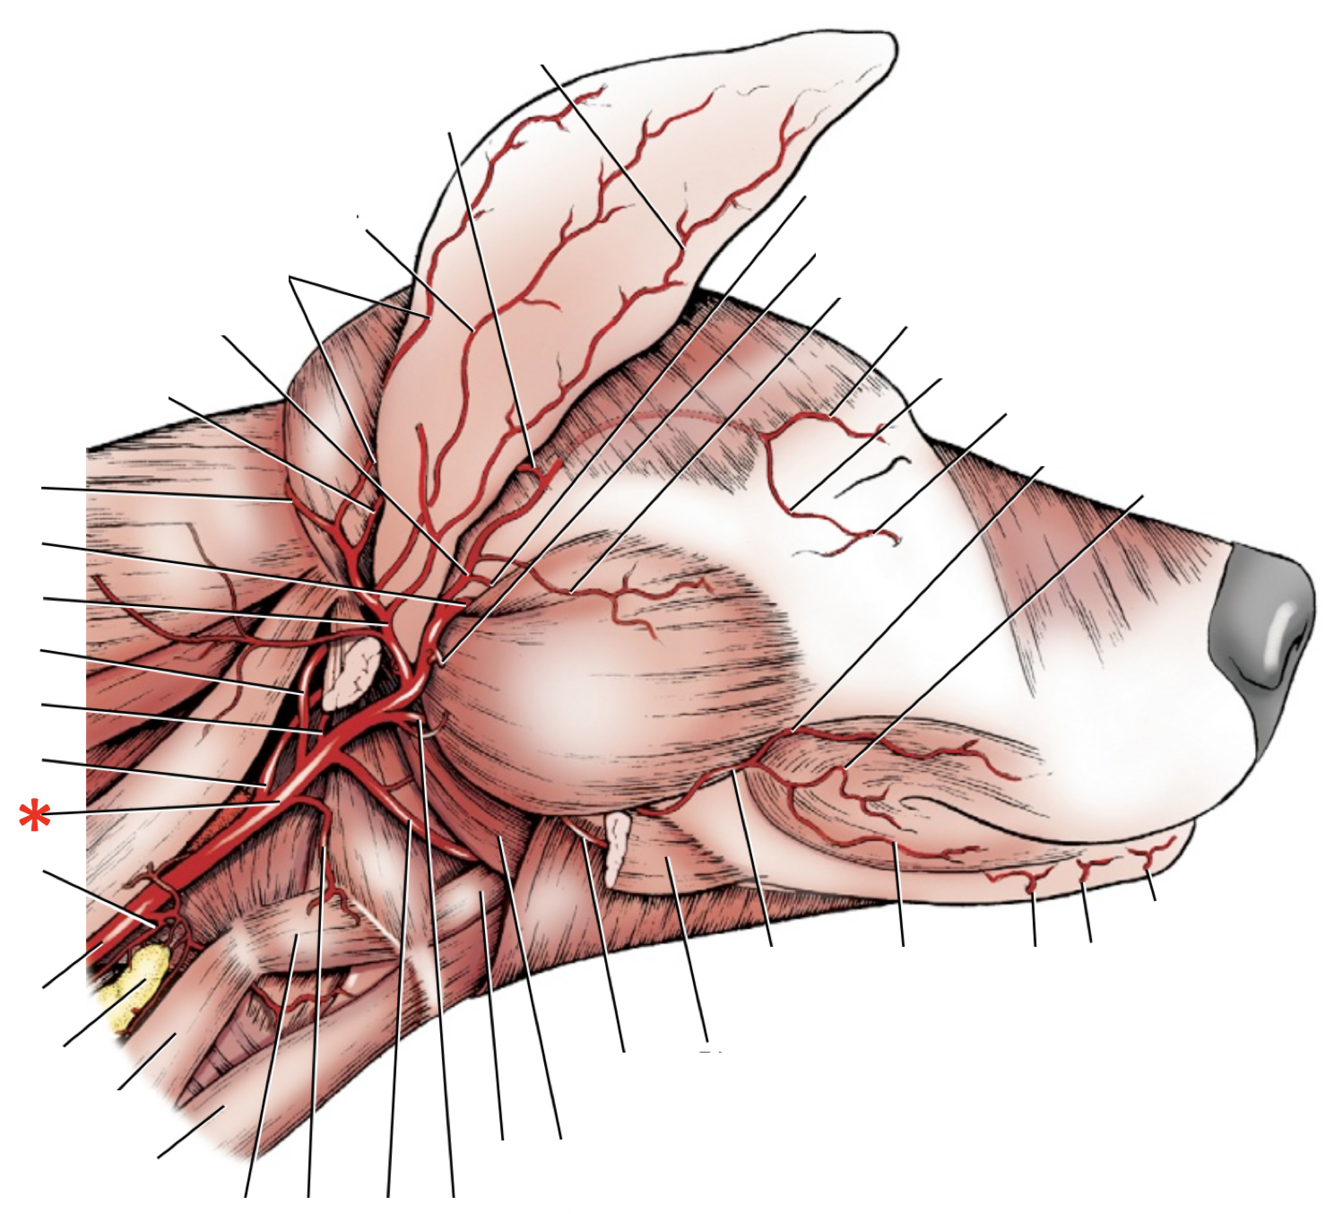

A. lingualis

A. facialis

A. maxillaris

A. auricularis caudalis

A. occipitalis

A. sublingualis

A. temporalis superficialis

A. facialis

A. cariotis externa

A. maxillaris

A. auricularis caudalis

A. lingualis

A. facialis

A. laryngea cranialis

A. maxillaris

A. occipitalis

A. carotis externa

A. laryngea cranialis

A. lingualis

A. facialis

A. sublingualis

A. auricularis caudalis

A. temporalis superficialis

A. maxillaris

**A.** **facialis**

**A.** **lingualis**

**A.** **carotis** **externa**

**A. lingualis**

**A.** **laryngea** **cranialis**

**A.** **auricularis** **caudalis**

**A.** **maxillaris**